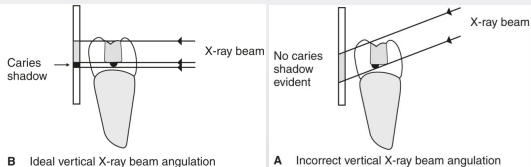

why is too much vertical angulation not a good thing

if looking at restorations particularly, if the angle is big → decay will be hidden under restoration

how is horizontal angulation a limitation of 2D imaging

change in angulation impacts ability to detect and stage carious lesions